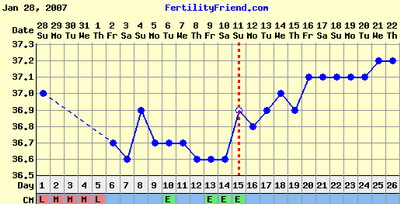

Kata, nagyon sajnálom, de szerintem 12-13 dpo-n még ne legyél elkeseredve, szerintem két-három nap múlva ha nem jön meg, tesztelj mégegyet mindenképpen. Nincs görbéd véletlenül?